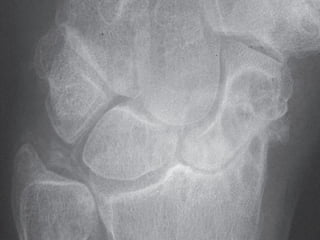

Plain Radiographs

:

Chondrocalcinosis It is classically seen in

-

Fibrocartilage (knee menisci, triangular

ligament of the wrist, symphysis pubis) →

punctate

Hyaline articular cartilage (knee, shoulder,

hip) → linear

linear

Tendon insertion sites (Achilles) → linear

IMAGING Plain Radiographs : Chondrocalcinosis Itis classically seen in - Fibrocartilage (knee menisci, triangular ligament of the wrist, symphysis pubis) → punctate punctate - Hyaline articular cartilage (knee, shoulder, hip) → linear linear - Tendon insertion sites (Achilles) → linear - Bursa